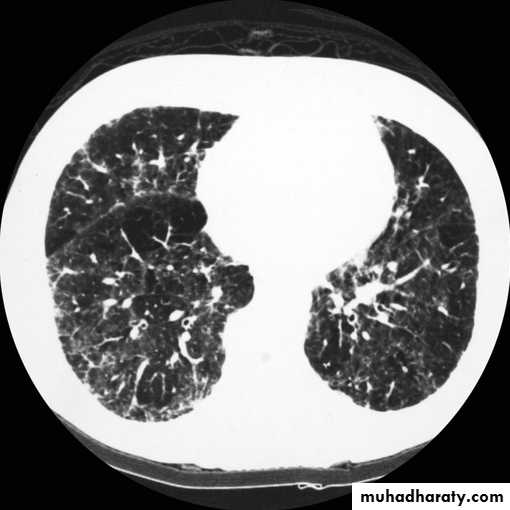

Bronchectasis

Abnormal irreversible dilatation of bronchioles with thickening of their walls . Presented with recurrent pneumonias & haemoptysis ..Types:Cystic

Fusiform

Cylendrical

In which the bronchiole is wider than the near by vascular branch

Causes –infancy & childhood infection

-TB

-pulmonary fibrosis

-cystic fibrosis

-immotile cilia syndromes